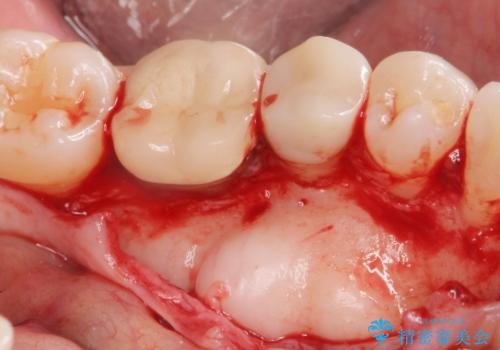

骨隆起除去

- 骨隆起が舌にあたり不快感があるので骨隆起をとりたくて来院。

静脈内鎮静麻酔下で骨隆起を除去を行いました。

骨隆起がなくなり不快感がなくなり大変満足して頂けました。

- 外科手術のため、術後に出血、痛みや腫れ、違和感を伴います